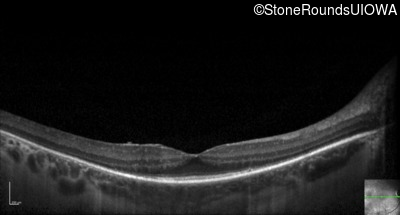

Optical Coherence Tomography - Right - 20/32 -1

Exemplar / OCT Stack